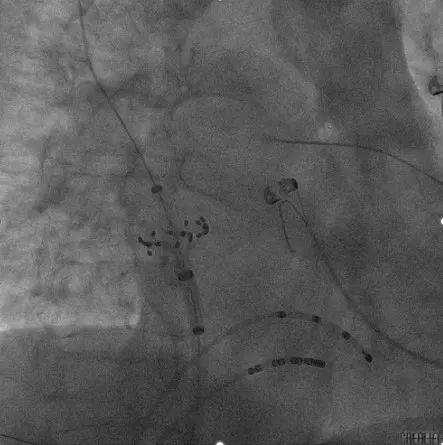

RSPV及RIPV消融:

RSPV口内消融

RSPV前庭位置消融

RIPV口内消融

RIPV前庭位置消融

术前术后心包对比:

术前心包基线扫描

术后心包检查

本次手术是在霆升心腔内超声指导下进行的脉冲消融手术。由于ICE提供的是实时且高清的图像,一方面可以清楚直视房间隔的位置,对于房间隔穿刺有很大的优势,另一方面术中医生可以实时观察到脉冲导管在肺静脉口部及前庭贴壁的情况,并且能实时监测到可能的并发症,如心包积液,从而显著减少了对放射线的需求。两者结合后,ICE指导下脉冲电场消融有望引领房颤消融进入新阶段。